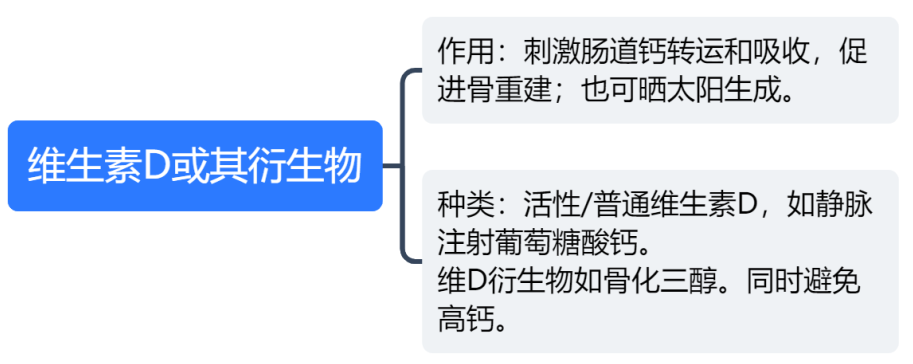

懒癌会复发吗? 甲状腺癌是最为常见的一种内分泌恶性肿瘤,近10年来,其发病率在全球持续快速上涨。约95%的甲状腺癌为分化型甲状腺癌 ( differentiated thyroid cancer,DTC) ,也就是俗称的“懒癌”,主要包括甲状腺乳头状癌( papillary thyroid carcinoma,PTC) ,甲状腺滤泡状癌( follicular thyroid carcinoma,FTC) 和嗜酸细胞癌( Hürthle cell carcinoma,HCC) 。 分化型甲状腺癌(DTC)的长期预后非常好,在10年随访中,成人DTC患者的生存率为92-98%。然而,5%-20%的患者出现局部或区域复发,复发时间从6个月至数十年不等,10-15%的患者继续发展为远处转移。甲状腺床和颈部淋巴结是DTC患者最常见的局部或区域复发部位,而远处转移主要见于肺和骨骼。

2. DTC复发风险度分层:术后是否需要行131I治疗?

复发风险分层以术中病理特征、淋巴结转移特征、分子病理特征及TSH刺激后(TSH>30mU/L)Tg(sTg)水平和131I 治疗后全身扫描(post-treatment whole body scan,Rx-WBS)等权重因素将患者的复发风险分为低、中、高危三层。利用这一分层系统指导是否对DTC患者进行131I治疗,以降低或控制复发风险。

复发风险低危的患者:原则上不推荐131 I治疗,可维持轻度TSH抑制治疗,定期随访监测。

复发风险中危的患者:是否施行131 I 需综合评估。

复发风险高危的患者:推荐行131 I治疗,是改善预后的重要手段。